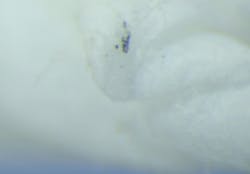

Figure 3a shows a cleaned, rolled swab prior to insertion into the implant screw channel. Figure 3b shows the outcome of this swab.

In total, seven out of seven samples yielded foreign material when swabbed (100%), resembling Ti particles and machine shavings. The particle size was estimated to be approximately 1–2 mm for larger shards (figures 3c and 3d) and around 20–30 microns for smaller particles (figure 4).